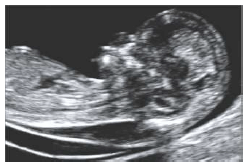

Sobre a imagem abaixo, podemos concluir que há, EXCETO:

maior associação com anomalias cromossômicas;

maior associação com malformação congênita;

maior incidência de óbitos fetais;

na maioria dos casos, regressão do achado e a criança nasce saudável;

elevada associação com doppler das aa. uterinas alterado.